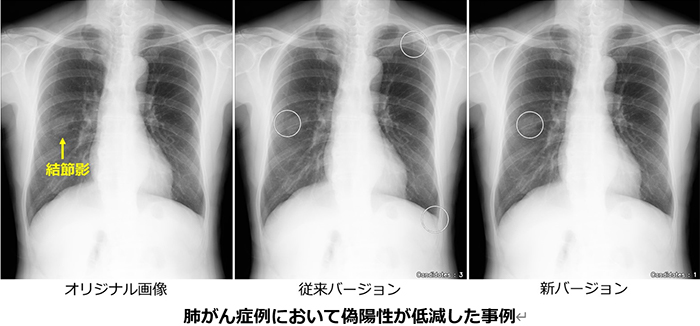

コニカミノルタの胸部X線画像診断支援ソフトウェア CXR Finding-i

専門医のスキルを学習したAIが胸部X線画像を解析し、医師による胸部X線画像の読影において、肺がんが疑われる所見である結節影、肺炎や結核などの所見である結節・腫瘤影の見落とし防止を支援するソフトウェアです。

AIの検出性能向上により医療現場の業務負荷軽減に寄与

「CXR Finding-i」は、専門医のスキルを学習したAIが胸部X線画像を解析し、医師による胸部X線画像の読影において肺がんなどが疑われる所見である結節影、腫瘤影や、肺炎や結核など感染症の所見である浸潤影をマーキングして見落とし防止を支援するソフトウェアで、2021年11月の発売以来、国内で約700の医療機関で導入されてきました。

一般的に画像診断支援AIでは、病変を見つける精度を示す指標である感度を上げていくと、実際には病変(陽性)ではない骨や血管が重なった影も病変候補としてマーキングしてしまう偽陽性率が増加して診断効率が下がります。そこで、病変を見逃さないようにしつつ、偽陽性率を抑制していくことが課題となっています。

今回の検出精度改良では、病変に対する感度は従来バージョンと同等の性能を維持しながら、病変のない正常例をAIが正常と判断した割合を示す特異度を従来の69%から88%まで大きく改善しました。病変検出性能の向上により診断の一層の効率化を図り、医師の負荷軽減に貢献するとともに、診断価値を高めます。

当院ではこの胸部X線画像診断支援AIの導入により、「診断の確実性」「見逃しを防ぐ安心」「読影効率の向上」「最新技術による信頼性」をご提供いたします。